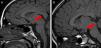

Brain magnetic resonance imaging (MRI) revealed a pedunculated HH, the size of which was 11mm in patient 1, 8mm in patient 2, and 17mm in patient 3, with all three of them located in the tuber cinereum (Fig. 1). All three cases responded well to treatment with a GnRH analogue.